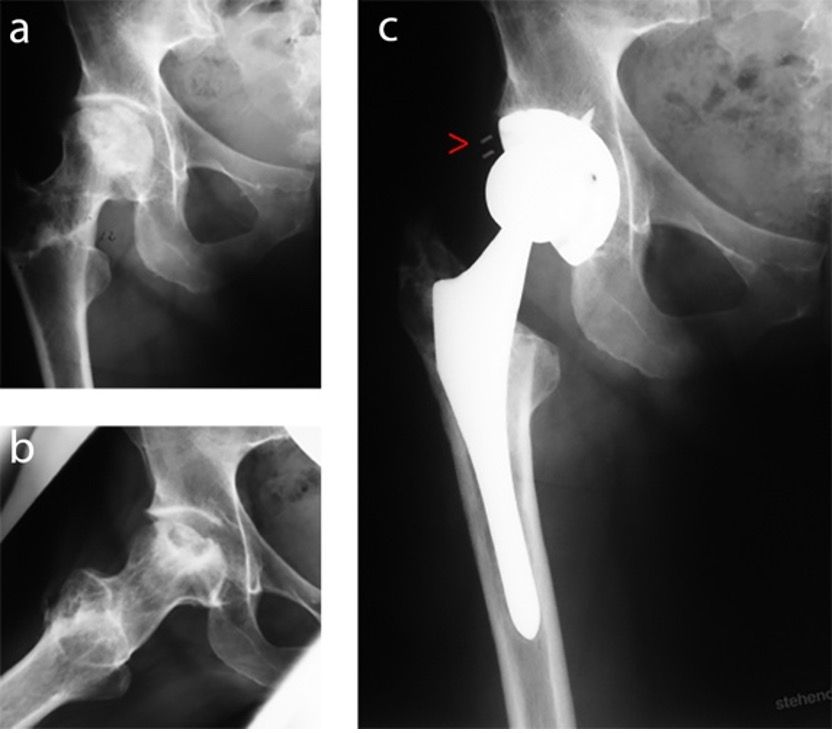

This is a case report on a 67-year old female patient. In the context of a bilateral secondary femoral head necrosis and after varising derotation osteotomy in 1991 she was implanted with a cementless ABG hip replacement in 1992. Figure 3 shows the preoperative findings and the postoperative implant position. Interesting in this context is the dysplasia inlay visible on the X-ray contrast strip with an exceptionally high inclination of the right acetabular component. As in the primary situation there is no indication of an acetabular bone defect in the unenhanced X-ray image after the ADC.

A follow-up examination with unenhanced X-ray after 10 years at the beginning of 2002 showed large peri-implant bone defects in the medial and superomedial region. The head appears significantly shifted from the centre suggesting severe polyethylene abrasion of the dysplasia inlay.

Figure 5 shows the diagnostic workflow using the ADS web App. Ultimately, a Type 1 C defect is identified prior to surgery. This type of defect features an intact and stable acetabular rim.

For the repair of the pronounced superomedial and medial defects, biological augmentation should be performed according to the principle of impaction bone grafting with the objective of biological downsizing [4, 7–9]. If the acetabular teardrop is intact, metallic augmentation is not necessary. However, the augmented bone must be under mechanical pressure, to ensure bone fusion. Therefore, a Burch-Schneider cage was implanted for this purpose. Figure 6 shows the postoperative findings with stable placement of the acetabular component on the dorsal column, the caudal hook in the obturator foramen and with a long acetabular dome screw, which imparts the major stability of the construction.